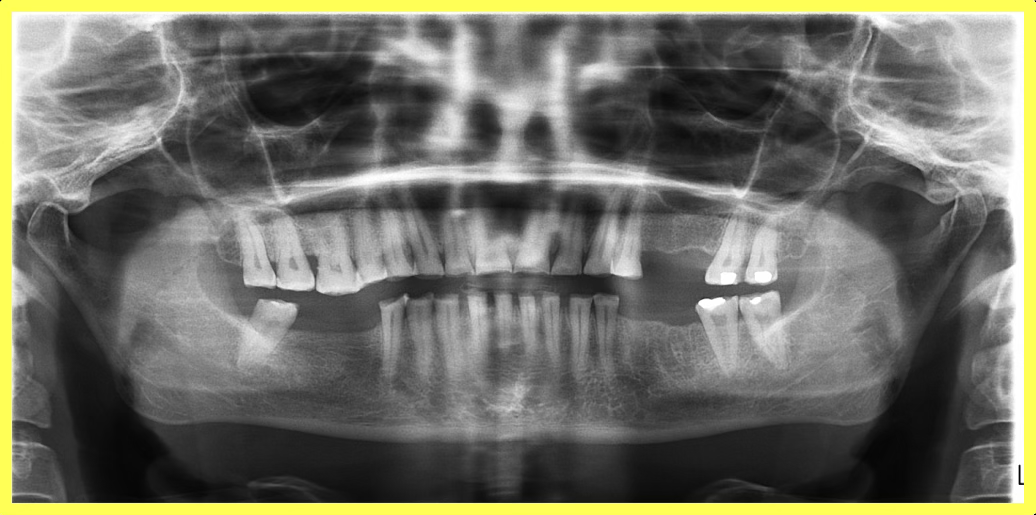

Initial condition

A 57-year-old female patient visited our dental center complaining of multiple missing and attrited teeth. On examination, patient had missing teeth 25, 26, 35, 36, 45 & 46 with grade 3 attrition. Treatment included impression-based muscle deprogrammer, Dio implants placement, PFM crowns for remaining attrited teeth, and delayed implant loading after 3 months.

Comprehensive oral examination with OPG X-ray. Patient presented with multiple missing teeth (25, 26, 35, 36, 45, 46) and severe attrition on remaining teeth. Muscle deprogrammer was fabricated and delivered.